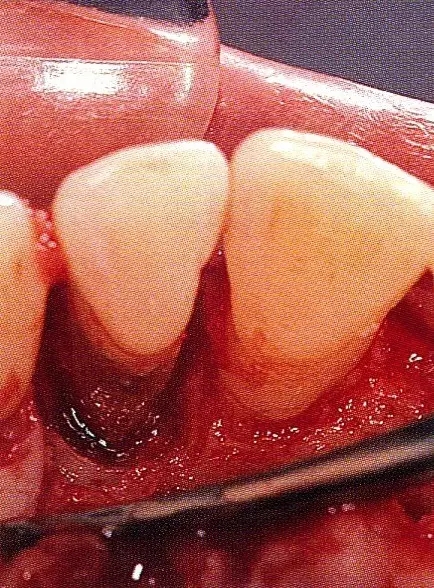

案例3   針對3壁性垂直性骨缺損使用非吸收性膜進行再生治療,再翻瓣時進行骨形態(tài)修整的病例。

▲圖7-1  左下6近中可觀察到3壁性垂直性骨缺損。此病例考慮到齦瓣供血關(guān)系,在前磨牙部位進行了減張切開,沒有進行縱切開。并利用刮治器、牙周外科用車針進行了徹底的骨缺損部位搔刮。